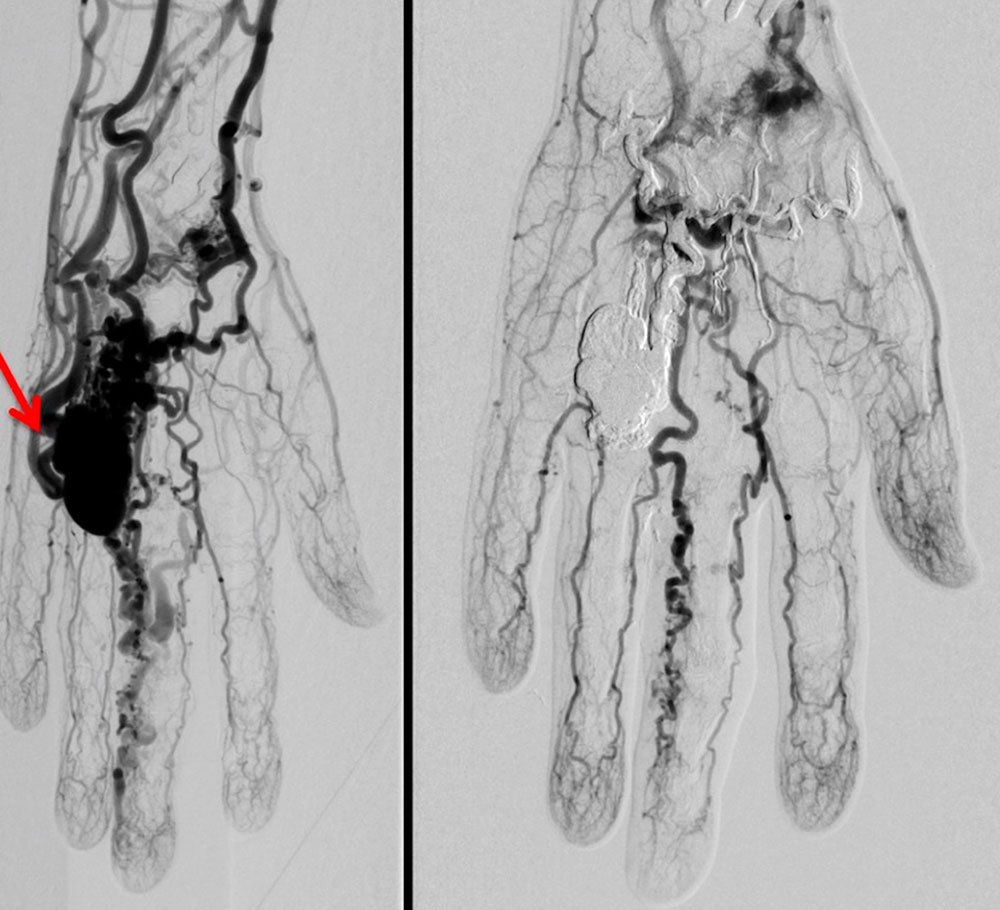

To eliminate an arteriovenous fistula as well as the shunts or the nidus of an arteriovenous malformation, endovascular therapy is normally the first choice. Relatively new techniques are available for this purpose with positive results regarding the long-term course of the disease. Depending on AVM localization and extension, these endovascular techniques can in some cases be combined with subsequent surgical resections (especially if there is a nidus with multiple fine fistulas). Primary resection of an arteriovenous malformation is usually not technically possible. The goal of endovascular treatment must always be selective and complete occlusion of the nidus while sparing the surrounding tissue. Endovascular occlusion of feeder arteries (e.g., with coils and plugs), proximal embolization or surgical ligation of feeder branches can often produce a temporary improvement, but this is later followed by worsening of symptoms due to the formation of new feeder arteries supplying the nidus and true proliferation of the lesion. A long-term therapy plan usually comprises several treatment sessions. Incomplete occlusion of the nidus leads to expansion of the arteriovenous malformation in the course of the disease and should therefore be avoided.

Percutaneous or endovascular embolization is still the therapy of choice. The nidus and the early drainage veins of the arteriovenous malformation are closed with permanent liquid embolic agents via a transarterial access and angiography. The liquid embolics are ethylene-vinyl alcohol copolymers, n-butyl cyanoacrylate (nBCA) or pure high-percentage ethanol.

The administration of these embolic agents requires a great deal of operator experience, since the arterial supply of the surrounding, unaffected tissue must be protected and displacement of embolic agents into healthy vessels must be avoided. If the angioarchitecture of the arteriovenous malformation permits, i.e., only a few drainage veins are present, embolization via a retrograde transvenous approach or a direct percutaneous approach is a very promising alternative. If it is technically and anatomically possible to completely occlude an arteriovenous malformation by embolization, a subsequent complete resection of the occluded nidus should be discussed. Additional resection of the occluded nidus may prevent recurrence in the long term. Additionally, resection may remove the remaining embolic material if it has a space-occupying effect.